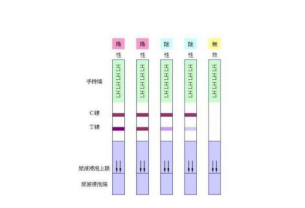

应用排卵试纸推断排卵期

首先要确定自己的月经周期,如果是周期28-30天,从月经周期第11天开始测试,每天检测一次,监测至阳性反应出现至消失,阳性反应考虑排卵期;如果月经周期短,那么检测的时间也需要提前,反之,如果月经周期长,那么检测时间也可以适当延长,通过家庭自测,以便安排生育计划,择期怀孕。